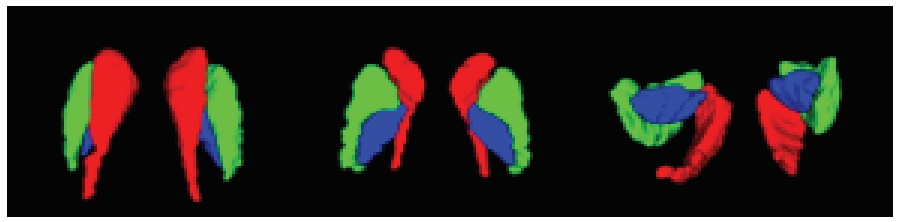

针对脑皮层下组织部分结构(如纹状体)在医学影像中目标小、对比度低,图像分割难度大,在自动医学诊断中应用比较困难的问题,本文基于深度学习的方法提出了一种医学图像分割网络,在磁共振成像中分割组成纹状体的苍白球、尾状核、壳核3部分。本文提出的网络模型具有捕获全局和局部特征的能力,并建立了全局与局部信息的相关性,在深度不退化的同时有效融合不同尺度的深层语义特征和浅层细节特征,实现对纹状体的精确分割。模型在公开的脑部数据集上进行了验证,并与其他先进的方法进行对比,结果表明本文的戴斯相似系数、平均交并比、95%豪斯多夫距离分别为94.26%、90.94%、3.82,均优于其他几种方法,达到了先进水平,这表明本文模型可以提高对纹状体的分割精度,为相关疾病的研究提供依据。